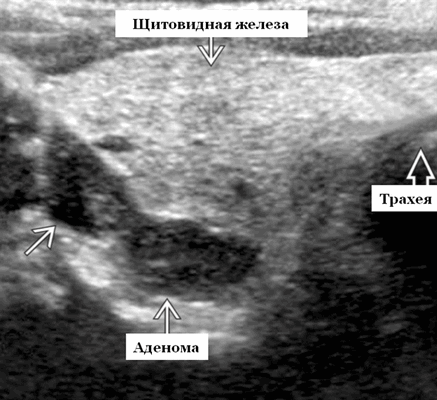

Опухоли паращитовидной железы на УЗИ

Ультрасонографические данные паращитовидной железы при опухоли

Серошкальное УЗИ. Гипоэхогенный узел позади доли щитовидной железы. Инфильтративная граница и кальцификация очень специфичны, наблюдаются в ~ 50% случаев. Толстая капсула гораздо чаще встречается при раке, чем при аденоме. Гетерогенность распространена, но наблюдается как с доброкачественными, так и со злокачественными опухолями околощитовидной железы. Кистозные изменения и неправильная форма неспецифичны.

Энергетический допплер. Нерегулярные сосуды, простирающиеся от периферии, скорее наводят на мысль о злокачественном, нежели доброкачественном поражении. Аденома паращитовидной железы, как правило, является гиперваскулярной с терминальным внутриопухолевым сосудом

Дифференциальная диагностика заболеваний околощитовидной железы на УЗИ

- Аденома паращитовидной железы обычно неотличима от карциномы. Интратиреоидальная, четко выраженная опухоль с переменной эхогенностью, перинодулярный сосудистый рисунок, кистозные изменения